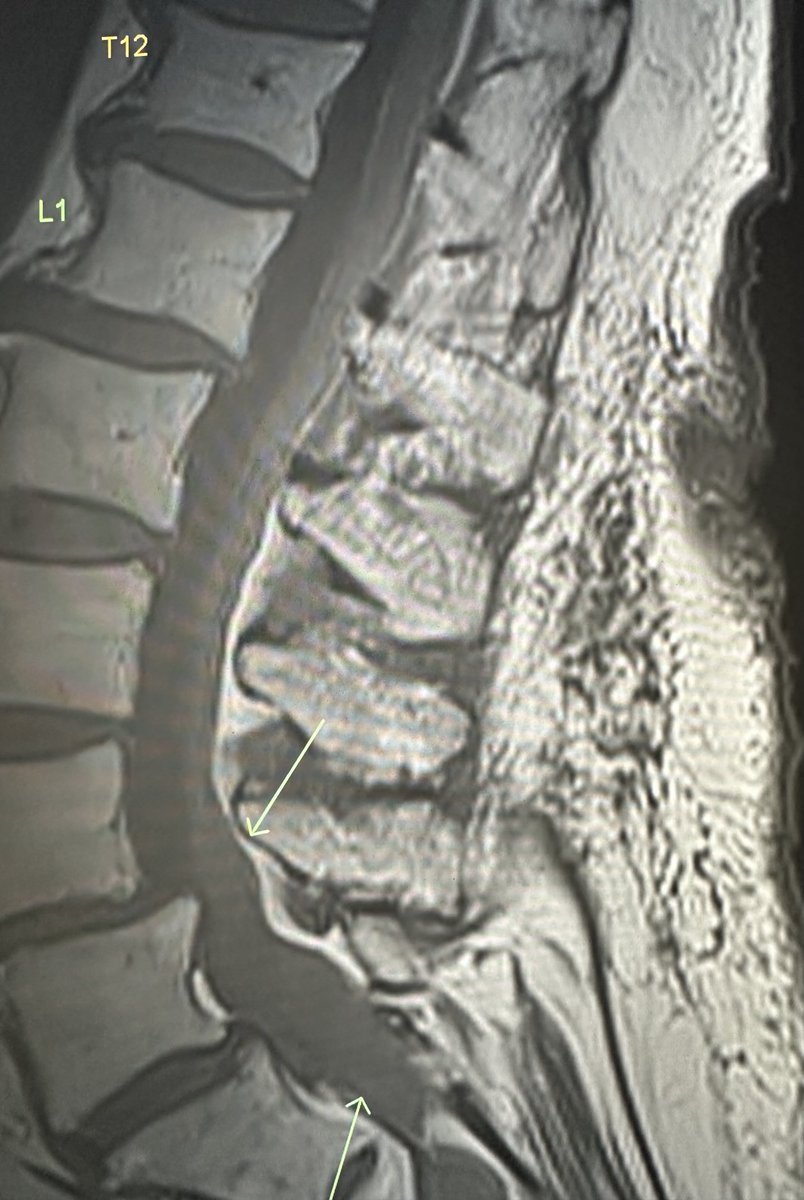

Elderly female. No interventions. New bilateral lower extremity weakness. Thoughts regarding this finding?

RJ tweet mediaRJ tweet mediaRJ tweet mediaRJ tweet media